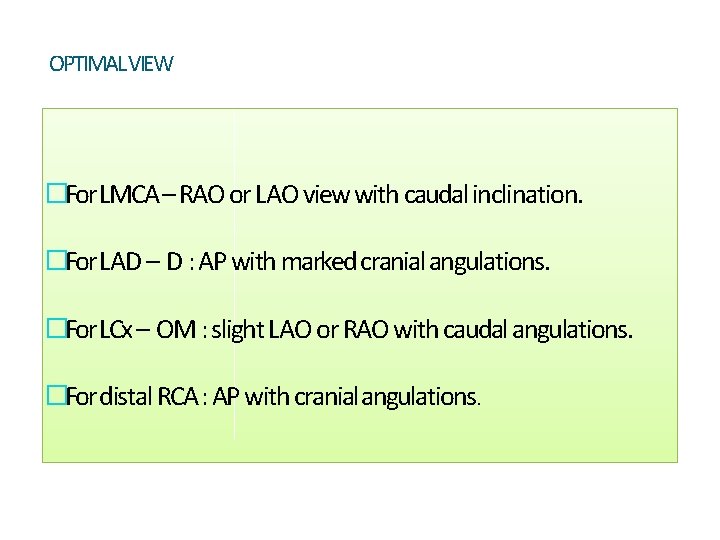

OPTIMAL VIEW �For LMCA – RAO or LAO view with caudal inclination. �For LAD – D : AP with marked cranial angulations. �For LCx – OM : slight LAO or RAO with caudal angulations. �For distal RCA : AP with cranialangulations.